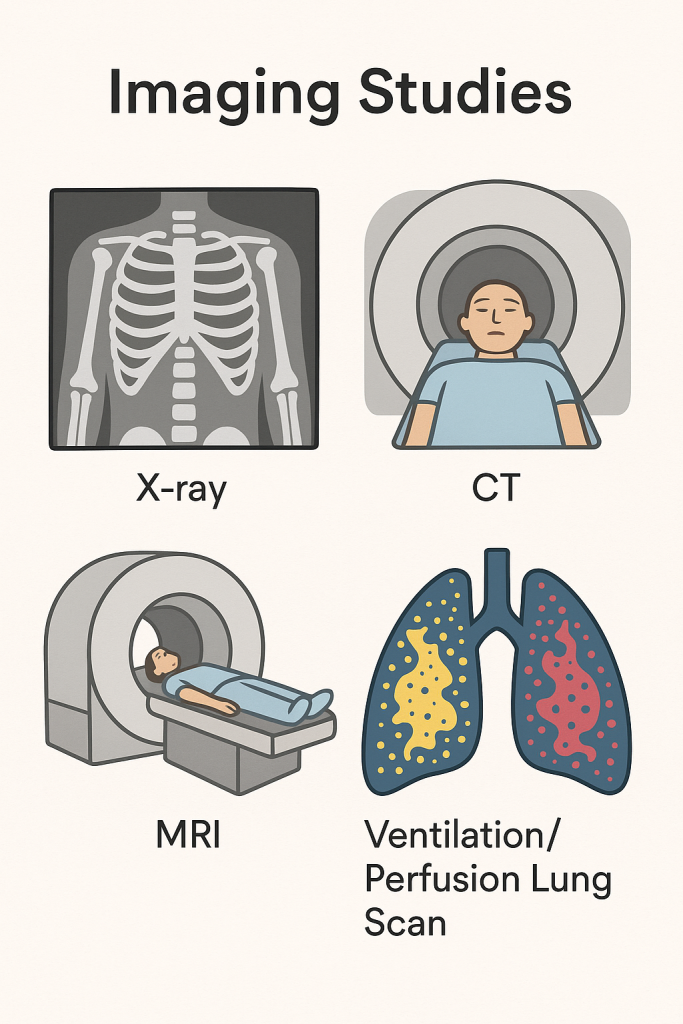

Imaging studies (ઇમેજિંગ સ્ટડીસ):

- ઇમેજિંગ સ્ટડી એ એનાટોમિક સ્ટ્રક્ચરને ઇવાલ્યુએટ કરવા માટે કરવામાં આવે છે.

- જેમાં એક્સરે, સીટી સ્કેન, એમ. આર. આઇ, એન્જિયોગ્રાફી અને વેન્ટિલેશન પરફ્યુઝન લંગ સ્કેનનો સમાવેશ થાય છે.

Chest x-ray (ચેસ્ટ એક્સરે):

- ચેસ્ટ એક્સરે માં સ્મોલ અમાઉન્ટ એકસ રેનો ઉપયોગ કરીને તે એરિયાનો 2D ઇમેજ ક્રિએટ કરવામાં આવે છે અને તેમાં બોન અને ટ્યુમરને વિઝયુલાઈઝ કરી શકાય છે.

- તેમાં મુખ્યત્વે એન્ટેરિયર-પોસ્ટેરીયર અને લેટરલ સાઈડનો વ્યુ લેવામાં આવે છે.

- એક્સ રે કરતા પહેલા પેશન્ટને ફૂલી ઇન્સ્પિરેશન કરવાનું કહેવામાં આવે છે તેથી લંગને સારી રીતે વિઝયુલાઇઝ કરી શકાય.

- એક્સ રેની મદદથી ન્યુમોનિયા, લંગ કેન્સર, ટ્યુમર, ફોરેન બોડી તેમજ રિબ્સ ફેક્ચરને આઇડેન્ટીફાય કરી શકાય છે.

CT-scan (સીટી સ્કેન):

- સીટી સ્કેન એ એકસ રે કરતા વધારે ડિટેઈલમાં માહિતી આપતું અને થ્રીડી ઇમેજ પૂરું પાડતું ઈમેજિંગ સ્ટડી છે.

- સીટી સ્કેનમાં બોડીના જુદા જુદા એન્ગલ થી એક્સ રે લેવામાં આવે છે અને કમ્પ્યુટરની મદદથી બોડીના ક્રોસસેક્શન પિક્ચરને ક્રિએટ કરવામાં આવે છે.

- સીટી સ્કેનની મદદથી ઓર્ગન અને સોફ્ટ ટીસ્યુની કન્ડિશન જાણી શકાય છે.

- સીટી સ્કેનથી લંગ કૅન્સર, પલ્મોનરી એમ્બોલિઝમ અને ઇન્ફેક્શન આઈડેન્ટીફાઇ કરી શકાય છે.

MRI (એમ. આર. આઇ):

- MRI – મેગ્નેટિક રેઝોનન્સ ઇમેજિંગ

- MRI માં પાવરફુલ મેગ્નેટ અને રેડિયો વેવ્સ નો ઉપયોગ કરવામાં આવે છે અને આપેલ એરિયાનો ક્રોસસેક્શન ઈમેજ ક્રિએટ કરવામાં આવે છે.

- MRI એ હાર્ટ, લંગ અને બ્લડ વેસેલ્સની ડિટેલમાં ઇન્ફોર્મેશન પૂરી પાડે છે.

- MRI ની મદદથી પલ્મોનરી નોડયુલ્સ, ફાયબ્રોસિસ, પ્લુરલ ડીઝીસ અને વાસ્કયુલર એબનોર્મલીટીને ડિટેક્ટ કરી શકાય છે.

Ventilation perfusion lung scan (વેન્ટિલેશન પરફ્યુઝન લંગ સ્કેન):

- વેન્ટિલેશન પરફ્યુઝન લંગ સ્કેન એ ન્યુક્લિયર મેડીસિન ટેસ્ટ છે જેની મદદથી લંગના એર ફલો અને બ્લડ ફલોને ઇવાલ્યુટ કરવામાં આવે છે.

- જેમાં રેડિયોએક્ટિવ સબટન્સને ઇન્હાલ કરવામાં આવે છે અને તેની મદદથી એર ફલો જાણવામાં આવે છે. તેવીજ રીતે ઇન્ટ્રાવેન્સ્લી રેડિયોએક્ટિવ સબટન્સ એડમિન્સ્ટર કરવામાં આવે છે જેથી બ્લડ ફલો જાણી શકાય.